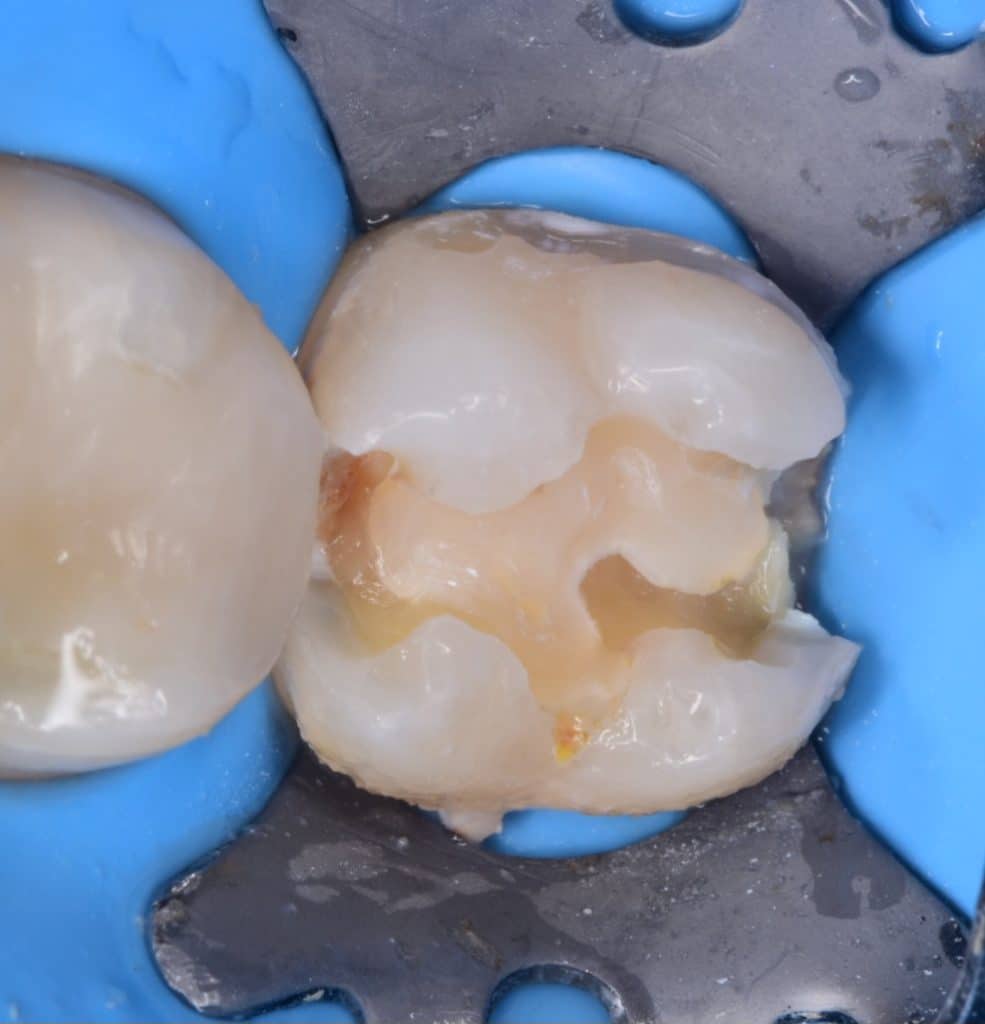

During cavity preparation

Because I don't use any magnification I can recognise this remaining composite so it's appear clearly by Camera

Final cavity design